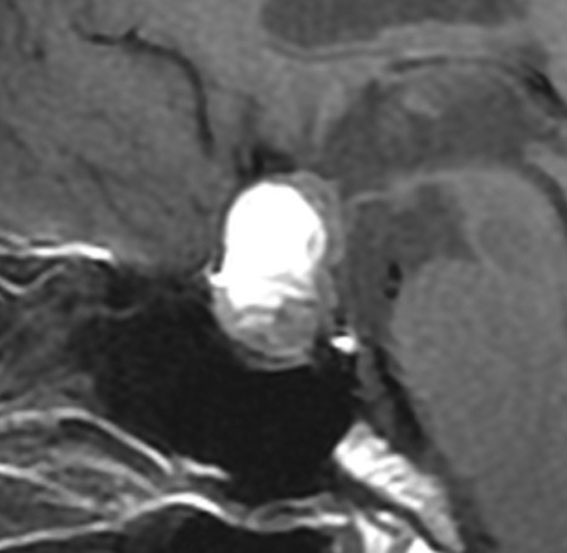

とても小さな腫瘍(微小腺腫) microadenoma

1cm以下の小さなものを微小腺腫といいます。ホルモンを異常に分泌する腫瘍は摘出する必要がありますが,そうでないものは治療の必要がありません。微小腺腫を数年観察しても増大する確率は10%くらいです。逆に,それ以上に大きなものだと,50%くらいの確率で増大します。

日本で汎用されているものでは最も解像力が高い3テスラMRIで撮影された,ガドリニウム増強像です。左側の画像では下垂体の大きさと形は正常に見えます。画像を調整すると,下垂体の内部,右端(黄色の矢印の先)に6mmくらいの小さな腺腫がみつかりました。MRIの性能がよくなったことによって数mmの小さなものも診断できるようになりました。